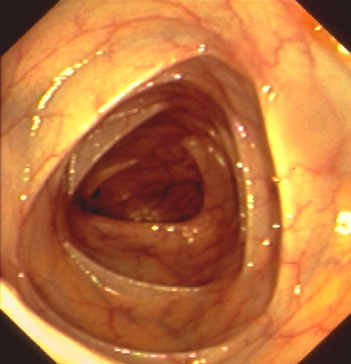

Die gastrointestinale Videoendoskopie ist heute die Standarduntersuchung für Erkrankungen der Speiseröhre, des Magens und des Dickdarmes.

Von allen Untersuchungen werden Bilddokumentationen angefertigt und in die Befundberichte eingefügt. Dickdarmpolypen bis zu einer bestimmten Größe können bei normaler Funktion der Blutgerinnung in der gleichen Sitzung mit einer Schlinge oder Zange entfernt und der histologischen Untersuchung zugeführt werden.